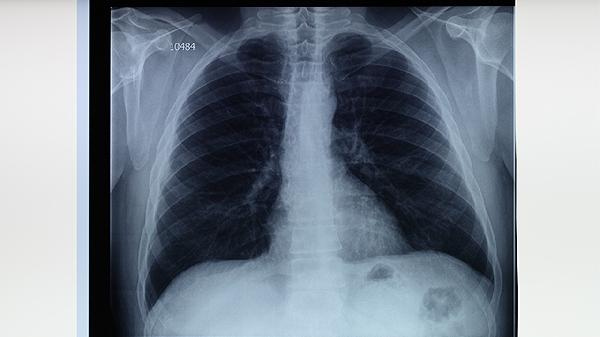

肺結(jié)核患者可通過高蛋白飲食、高維生素飲食、適量碳水化合物、充足水分?jǐn)z入、避免刺激性食物等方式進(jìn)行飲食調(diào)理。肺結(jié)核是由結(jié)核分枝桿菌感染引起的慢性傳染病,合理飲食有助于增強(qiáng)免疫力并輔助治療。